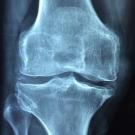

A bone density test can inform you how effective an osteoporosis medication is for your patients. How soon after medication initiation would you perform a bone density test?

Do women have a higher fracture-related mortality rate than men? Take our quick quiz and find out!

Test your knowledge on the disease that results from a loss of blood supply to the bone by taking this short quiz based on facts from the National Institute of Arthritis and Musculoskeletal and Skin...

New criteria for risk stratifying patients with osteoporosis were included in the 2020 updated AACE/ACE guidelines. How familiar are you with the criteria? Take our quick quiz to test your knowledge!

Osteoporosis screening with bone measurement testing to prevent osteoporotic fractures should be performed on which patient population? Take the quick quiz and find out!